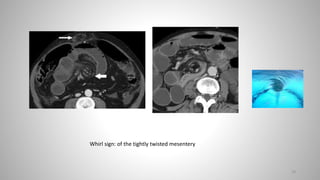

• “Whirl sign": of the tightly twisted mesentery

'U' or 'C' shaped loops of bowel.

Point of obstruction has a beak-like appearance

Closed loop obstruction with radial array of dilated loops.

There is bowel wall thickening and mesenteric edema indicating ischemia

Whirl sign: of the tightly twisted mesentery